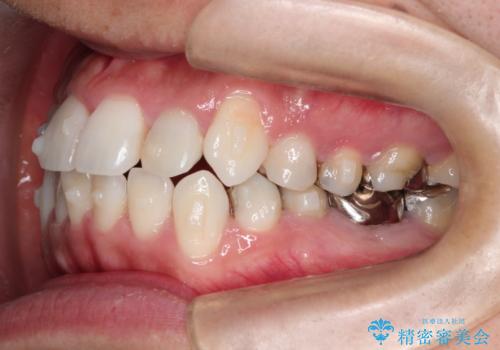

インビザラインで目立たない矯正 ガタガタの歯並びをきれいな歯並びへ

- 全体的なガタガタが気になるとのことで来院されました。

歯と歯のあいだをわずかに削りスペースを作り、ガタガタを改善する計画としました。

装着時間をしっかり守っていただけたのでスムーズに治療をすすめることができました。